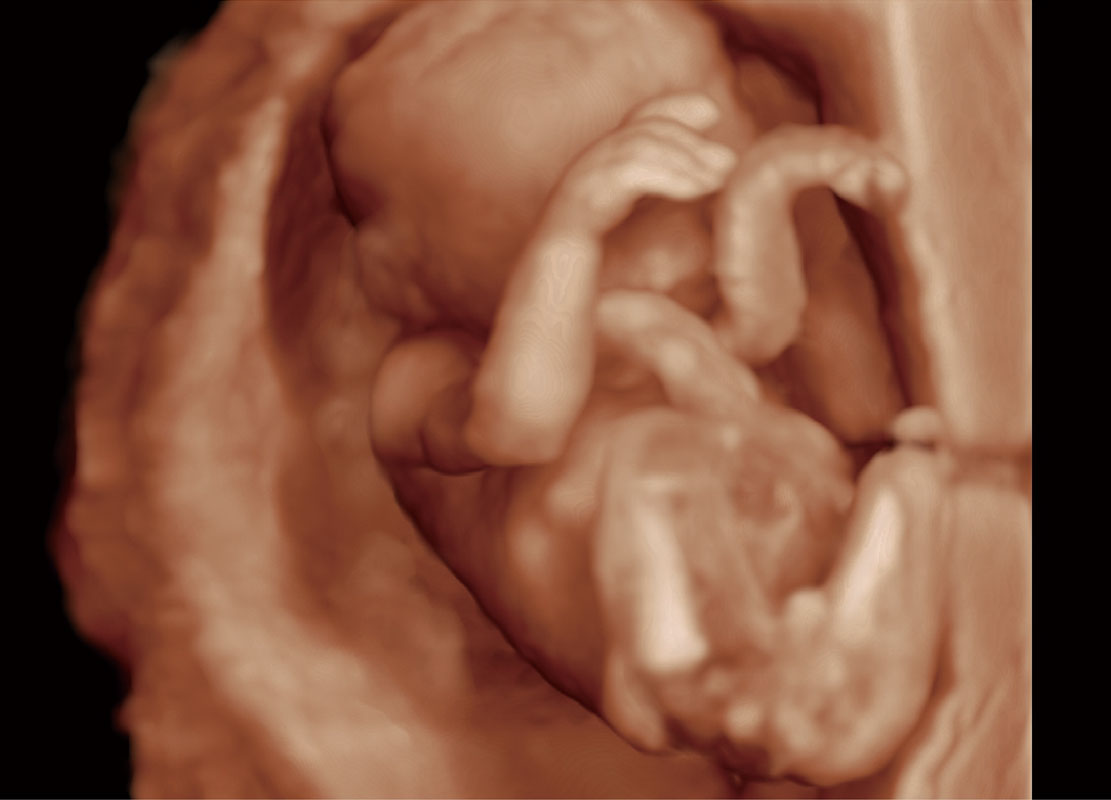

高分辨率容积成像-早孕胎儿

光影成像-孕囊

P60提供简单易学易用的高端诊断工具,为您中晚孕筛查提供快速清晰的解剖信息。

S-Fetus能够助您在实时扫查过程中自动识别标准切面、自动测量并录入报告。一个按键,即可快速、高效地获取胎儿生理指标,简化您的产科检查操作。